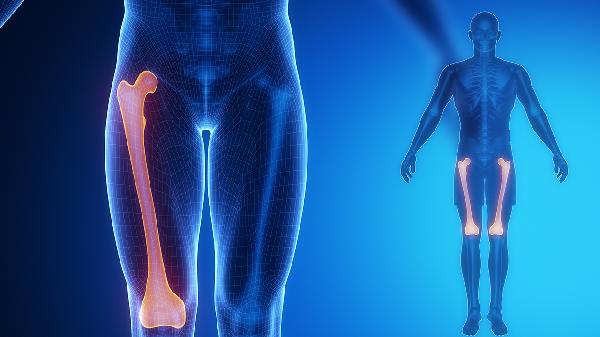

该药含黄芪、当归等补气活血成分,可促进局部血液循环,缓解气血不足引发的关节酸软无力。常见于中老年人或劳损性关节炎,伴随面色萎黄、活动后疼痛加重。需避免与抗凝药物同用。